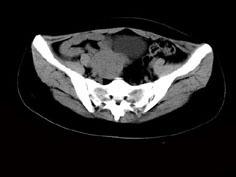

问题 女,24岁,近月余感尿频明显,CT检查如图,最可能诊断为 ( )

选项 A、盆腔纤维瘤 B、卵巢囊肿 C、子宫肌瘤 D、卵巢癌 E、膀胱癌

答案 A